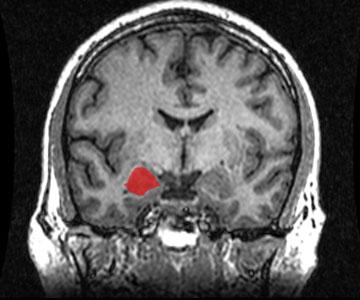

COVID-19 and Loss of Brain Mass

Jessica Bernard

Biology

Medicine

Spotlight